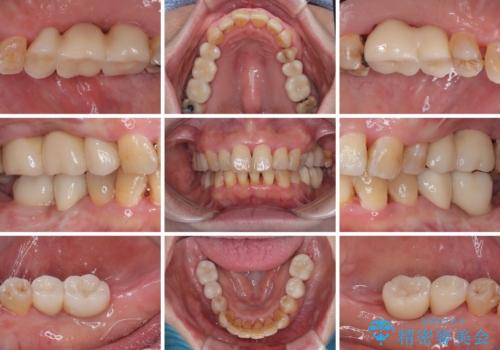

最終的に奥歯はオールセラミッククラウンによる補綴治療を行うこととしました。

治療前は磨き残しが多く見られ、全体的に歯肉が腫れている状態でしたが、抜歯の必要な歯を抜いたことで口腔内の環境が改善され、磨き残しも少なくなってきました。

インプラントにより咬合が回復したことで、治療開始時に認められた上顎前歯の動揺も改善されました。